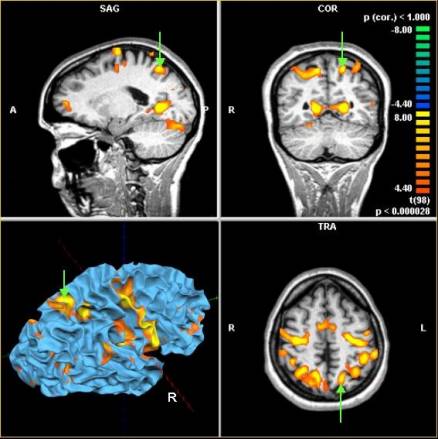

NeuroImaging:

functionele MRI